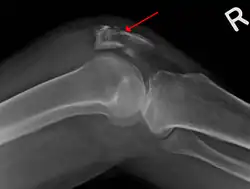

La radiographie déterminera s'il y a oui ou non bel et bien une fracture de la rotule. Si oui, le chirurgien orthopédiste pourra décider d'opérer.